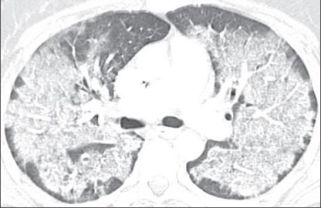

3.患者平素体健,近几日发热,咳嗽,CT如下:

这个蝶翼征太典型了,心衰合并肺部感染?

NO!像心衰,不一定是心衰。

抗细菌感染,病情好转。

这就是一个单纯的肺部感染!蝴蝶想他了。